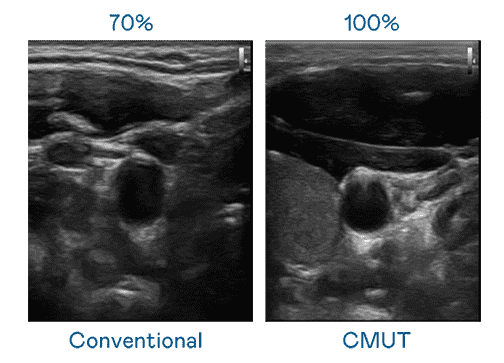

CMUT 技术是一种用电容式微机电元件来产生超音波讯号的技术。。。与传统 PZT 压电式技术相比,,,CMUT 频宽增加 30%,,,更宽频的超音波讯号让影像解析度大幅提升,,,是实现高影像品质医疗超音波扫描、、、促进精准医疗发展的关键技术。。。。

超音波影像的解析度高低,,,首先取决于探头能发出的讯号频宽。。。。尊龙集团 CMUT 可提供高清晰的超音波讯号,,,提供高频宽、、、高灵敏度、、影像纹理细节更高的超音波影像,,,,协助医护人员缩短影像判读时间及利用精准的医疗影像进行诊断。。。